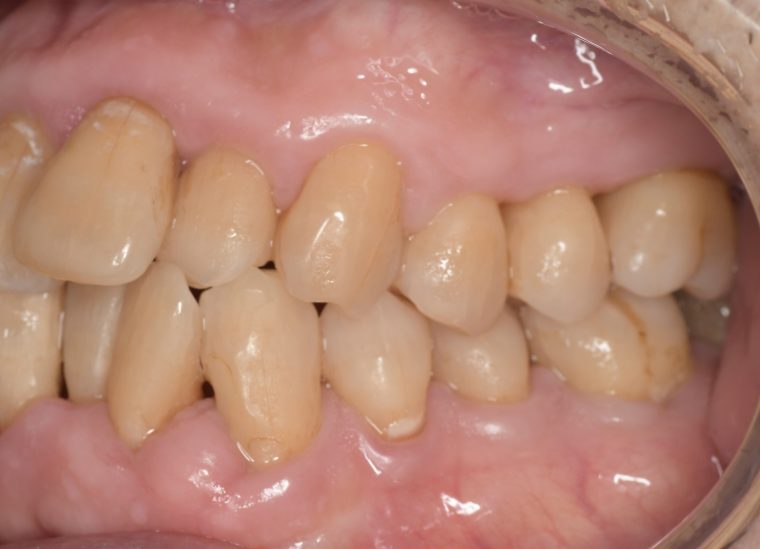

CASE 14

下顎before

下顎after

臼歯before

臼歯after

基本情報

| 年齢・性別 | 27歳・男性 |

|---|---|

| 主訴 | 歯石とりたい |

| 治療内容 | スケーリング |

| 治療期間 | 30分 |

| 治療費 | 約1,500円(保険診療) |

| リスク・副作用 | 知覚過敏、歯肉退縮、出血 |

| 治療方針 | 歯列不正でプラークがつきやすいため、TBIを行い定期的に歯石を除去していきます。 プラークコントロールが出来るようになったら定期検診でクリーニングを行っていきます。 |